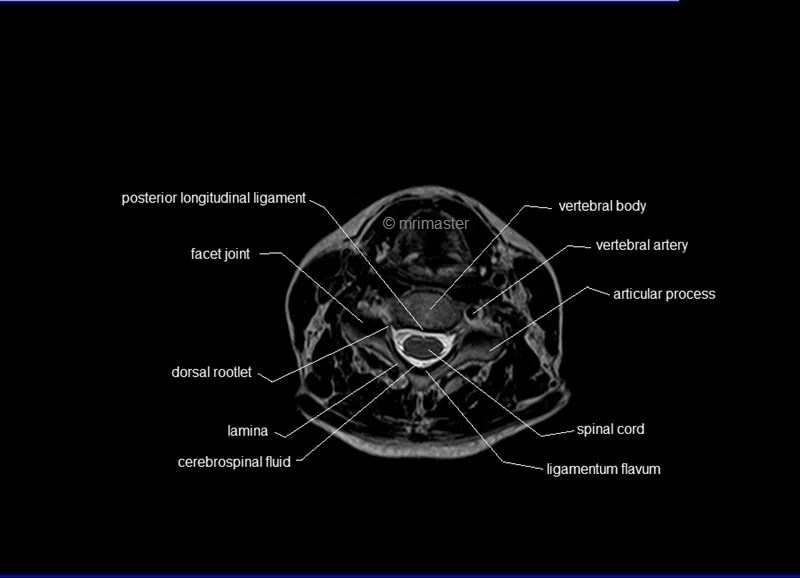

MRI Spine Anatomy Free MRI Axial Cervical Spine Anatomy Mri Anatomy Axial Use the mouse scroll wheel to move. It enables clinicians to focus on various parts of the brain and examine their anatomy and. It is the most complete reference of human anatomy available. Note, however, that mcrae’s line (basion. Mri scans, much like computed tomography, typically produce three anatomical views; Mri axial cross sectional anatomy of brain. A brain mri. Mri Anatomy Axial.